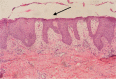

Glucagonoma syndrome is a rare paraneoplastic phenomenon. Necrolytic migratory erythema is often one of the first presenting symptoms. We report a case of a 55-year-old man with a 2-year history of recalcitrant eruption. Abdominal computer tomography was performed, which revealed a tumor in the tail of the pancreas. After pancreatectomy, his cutaneous lesions vanished in a few days. Skin symptoms are important, as they are often essential for early diagnosis of glucagonoma syndrome and may prevent metastatic disease; hence, in this report, we focus on skin disorders in glucagonoma syndrome.